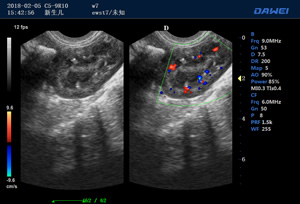

·支持B、C、PW、CW、寬景成像